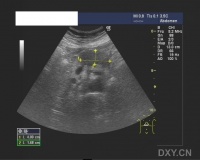

B超检查[编辑 | 编辑源代码]

B超检查是诊断胰假性囊肿的一项简便而有效的手段,典型者于上腹可探及一位置明确、范围肯定的液性暗区。B超对鉴别包块和囊肿特别有助,对胰假性囊肿的诊断正确率可达73%~91%。动态的超声探查可了解囊肿大小的改变。此外,在B超引导下,可作囊穿刺,抽取囊液作生化细胞学检查。